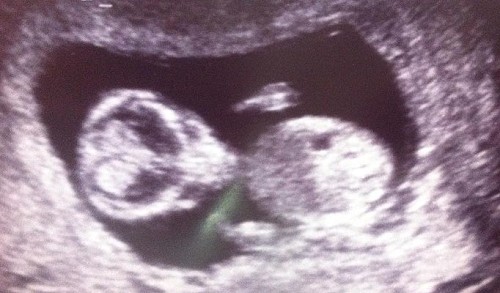

產檢超音波 照出外星人

繼上個月一對夫妻進行產檢超音波掃描時照出可愛的鴨子後,英國的狄恩夫婦(Scott & Larissa Dean)日前進行超音波產檢時,照片讓他們嚇了一跳,因為太太的子宮裡清楚的看到一個橫躺的外星人臉。

23歲的史考特狄恩笑著說:「我一看到照片,就轉頭問太太『妳是不是和外星人有一腿』」。